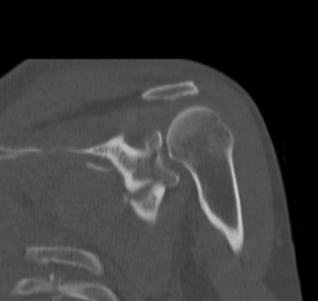

Case 1

- > 1 cm medial displacement

- ORIF via posterior / modified Judet approach